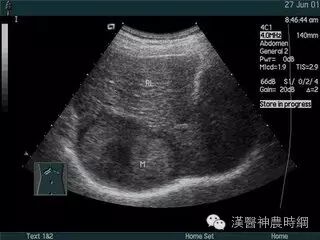

1.超声检查  B超检查用于肝癌诊断具有无损伤、无放射损害、简便、价廉、敏感度高、可重复性等优点。它可显示肿瘤的大小、形状、部位、肿瘤与血管的关系以及肝静脉、门静脉有无癌栓等,其诊断符合率可达90%。B超可检出1~2cm的小肝癌,最小直径为0.5~0.7cm。文献报道高分辨力B超对0.5~2.0cm的肝内微小灶的发现率较高,但定性诊断的准确率仅为58%。近年国内外均有人采用超声对比剂,如铁或钆等行声学造影,有助于定性诊断和确定病灶大小。原发性肝癌B超图像常显示肝体积增大,病变向肝表面隆起,周围常有声晕等。其回声可表现为低回声型、高回声型和混合回声型。小肝癌常呈低回声型,大肝癌或呈高回声,或高低回声混合,并可见中心坏死液化的无回声区。B超检查可因肺、胃等器官遮盖存在盲区,造成遗漏病变,如右膈下、左外叶上段等。微小病变位于肝实质深部并伴有严重肝硬化时,常难以辨认。另外与操作者的经验和检查是否细致均有关。